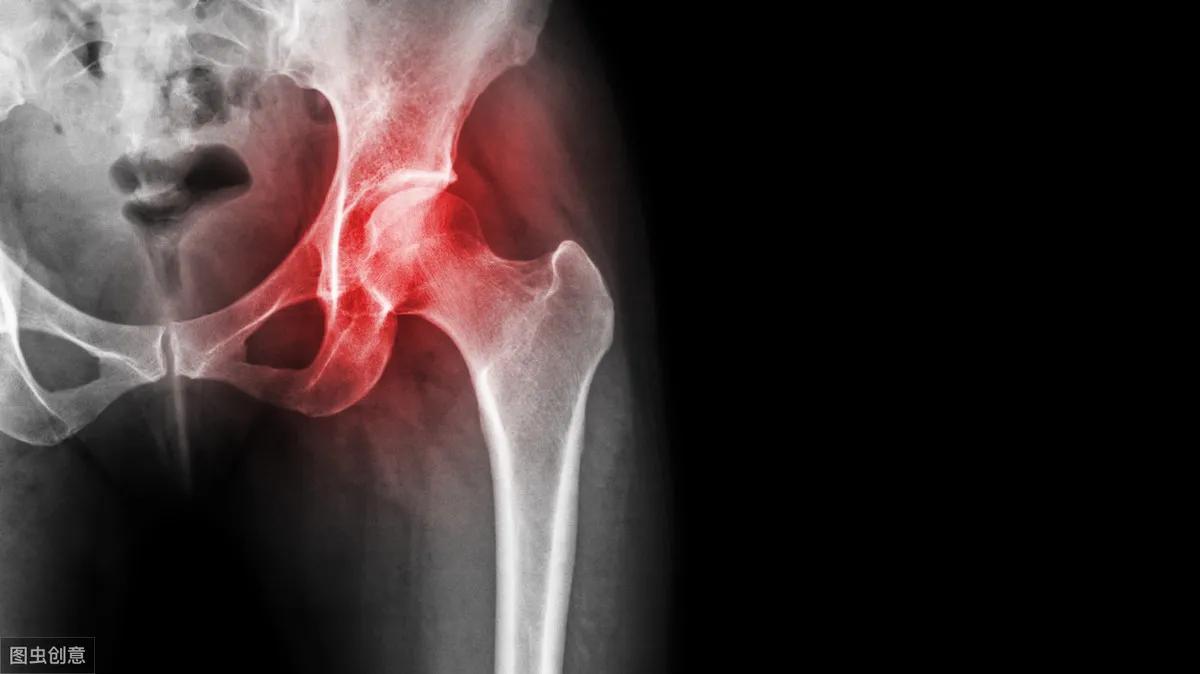

髋部在哪?髋部就是我们平时所说的「胯部」,髋关节一边是股骨,一边是盆骨,股骨头和髋臼构成了髋关节,它承载了人体上半身的重量,影响人的站立和行走。

如此重要的地方,倘若出现问题,影响的就是老人的整个生活了,进行治疗是必要的,但与此同时,很多问题便一一浮现出现了,其中一个便是该选择保守治疗还是选择手术治疗?